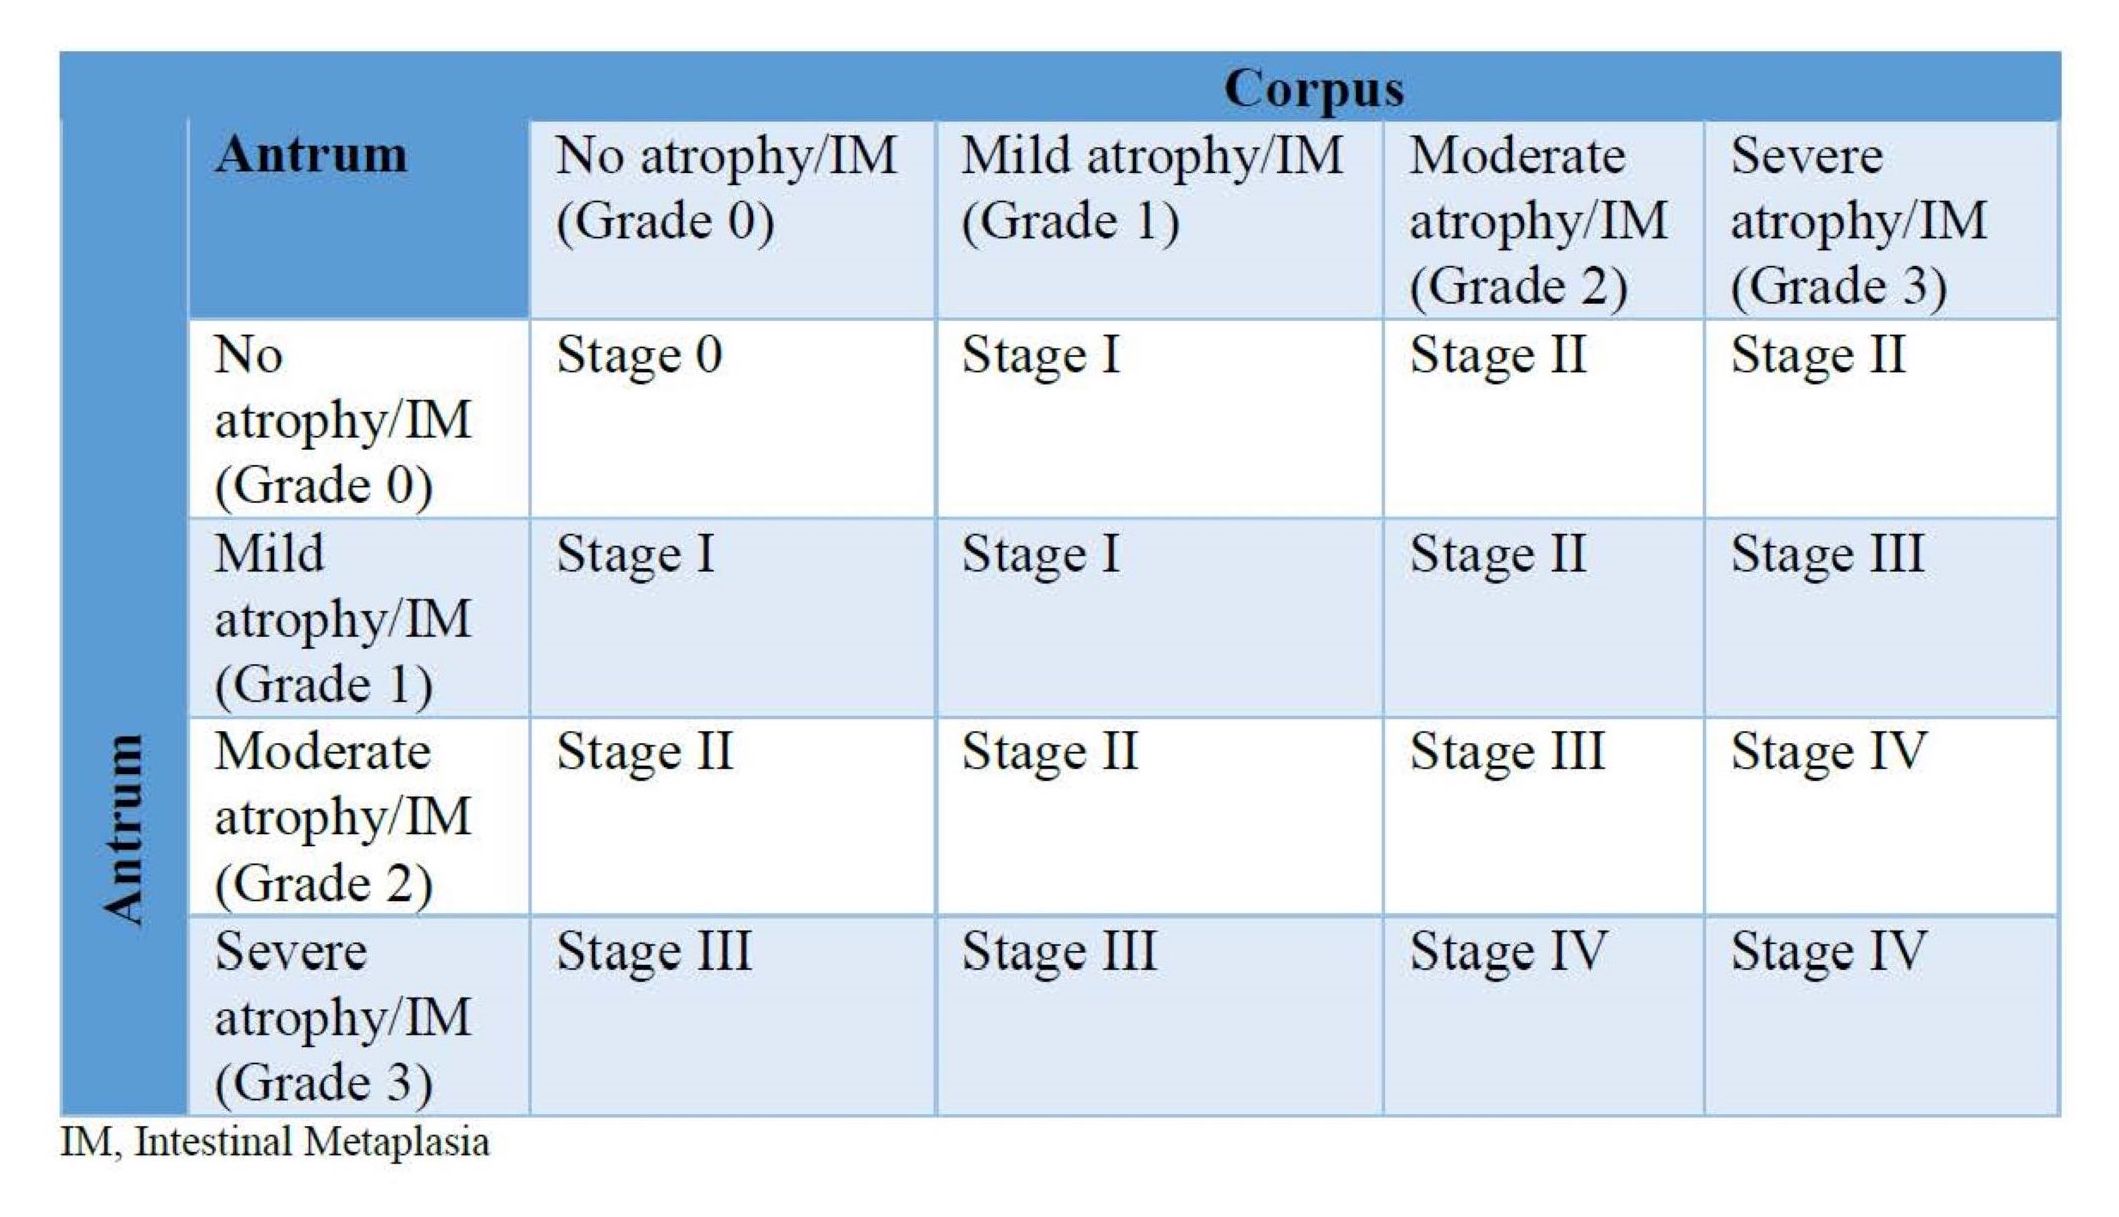

- Operative link for gastric intestinal metaplasia (OLGA / OLGIM) stages III / IV are considered high risk factors for gastric carcinoma

- OLGA / OLGIM stages III / IV

- Intestinal metaplasia is staged using the OLGA / OLGIM system; it is based on the grades of intestinal metaplasia in the antrum (including incisura) and body

- OLGA / OLGIM stages III and IV are considered as high risk for progression to gastric cancer (Gastrointest Endosc 2010;71:1150)